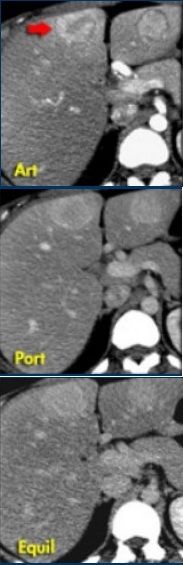

Diagnóstico = adenoma

Um adenoma é regularmente caracterizado por sangramento, gordura ou peliose. Embora não possamos ver a própria peliose, ela pode resultar em uma lesão hiperintensa no T1. Na imagem, dois incidentalomas. Decida por si mesmo porque estas não são lesões de FNH. Na fase arterial, existem duas lesões hipervasculares, um pouco menos densas do que seria de esperar na HNF. Ambas as lesões demonstram um halo de uma cápsula, que não deve ser aparente na HNF. Diferentemente da HNF, o realce não é homogêneo e na fase de portovenous e equilíbrio as lesões não são isodens para o fígado.